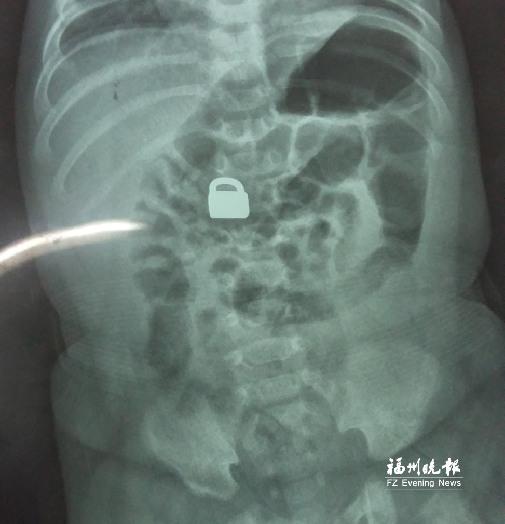

7.25龙岩当地医院拍的X光片显示,平安锁在宝宝体内。

“X光片显示,那是一把1.5厘米×0.9厘米的平安锁,有指甲盖大小,已经到了宝宝的小肠处。”7月28日,陈惠萍见到宝宝时,吃了一惊,“他真的好小,被抱在妈妈怀里,眼睛微微睁开,我估计他的世界还是混沌的,没想到就已经接受了这么大的挑战。”

宝宝排出的平安锁,有指甲盖大小。